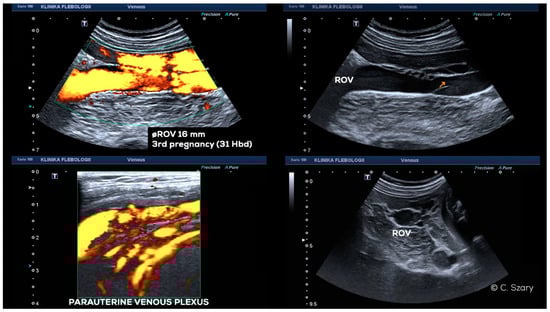

4.2. Grading of Ovarian Veins Insufficiency

4.2.2. Grade I/II (GI/II)

4.2.3. Grade II (GII)

4.2.4. Grade II/III (GII/III)

4.2.5. Grade III (GIII)

4.2.6. Grade IV (GIV)